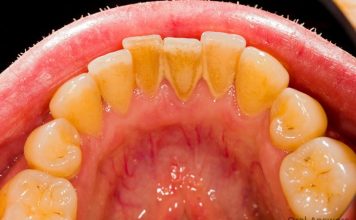

U današnjem članku vam pišemo na temu kako možete efikasno ukloniti zubni kamenac koristeći prirodne sastojke koje sigurno već imate kod kuće. Saznajte...

Problem kamenca...